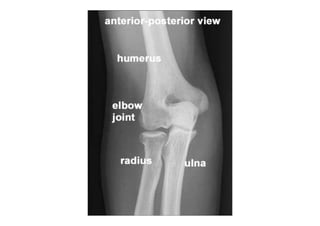

RADIOLOGIA DO

TRAUMA DO ESQUELETO

Referência: http://www.accessexcellence.org/RC/VL/